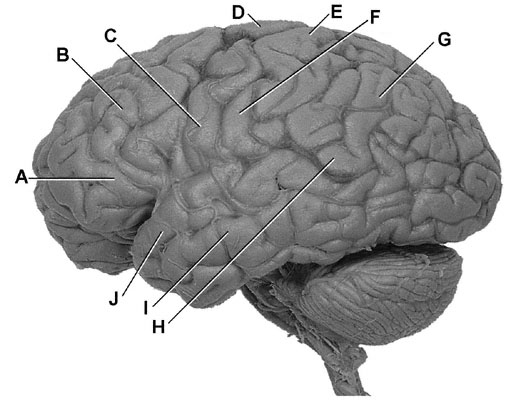

A 43-year-old man has weakness of the right lower two thirds of the face. Which of the following labeled sites on the photograph of the left hemisphere shown is most likely to be damaged?